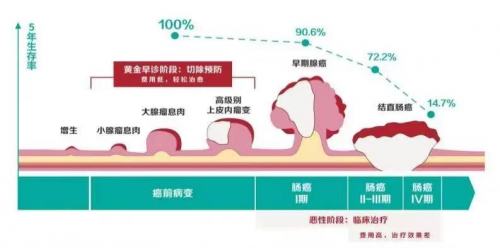

警惕!这5种慢性炎症若不及时治疗,竟可能演变为癌症!炎症,作为一种机体对抗损伤或感染的自我防护机制,常被视为良性生理过程。 然而,持续的炎症反应一旦转变为慢性,便可能演变为对健康的隐形威胁。 尤其值得注意的是,以下5种慢性炎症若得不到及时有效的治疗,甚至有可能演变成癌症。 1. 慢性胃炎:胃癌的潜在催化剂 由于幽门螺杆菌...

短短一年炎症变癌症?提醒:碰上4类炎症不可拖,以免演变成癌每年1270万新癌症患者约六分之一是因感染病毒、细菌和寄生虫造成,这些感染导致了身体出现了长期的慢性炎症,时间长了,自然也就诱发癌症了。 所以,换句话说,慢性炎症是导致癌症的罪魁祸首,这并不夸张,作为医生,要提醒大家的是,碰上4类炎症不可拖,以免演变成癌。 第一,慢性萎缩...

不到一年时间,炎症变癌症了!医生坦言:患上3种炎症,尽早检查并最终演变为癌症。炎症的背后是什么?它和癌症如何联系在一起?炎症与癌症:看似无关的隐形杀手从医学角度来看,炎症是机体的一种基本保护反应机制。当身体遭受损伤或面临感染时,免疫系统会立即启动,旨在清除病原体并促进受损组织的修复。然而,我们必须认识到,这一机制并非绝...

短短一年炎症变癌症?医生提醒:患上4种炎症不能拖,小心癌变进而演变为癌症。就像是一颗慢慢发芽的毒瘤,早期无声无息地潜伏在体内,等到我们意识到时,病情已难以挽回。2018年,50岁的李女士因为长期... 如何预防这些炎症转变为癌症?炎症是人体的一种自我保护反应,但如果不及时控制,慢性炎症可能会成为癌症的温床。预防这些炎症引发癌症,首...

很多癌症都是自己拖出来的!提醒:这几种炎症别忽视,早治早好你有没有听过这样一句话:“健康就像存钱,平时积累一点点,关键时刻才有用。”可很多人不在乎,一直透支自己的身体,结果问题一拖再拖,等到检查出癌症,才发现后悔已经来不及了。 有些病,早发现早治疗,其实根本不至于演变成癌症,特别是一些小小的炎症,你有没有想过,那些看似不起眼...